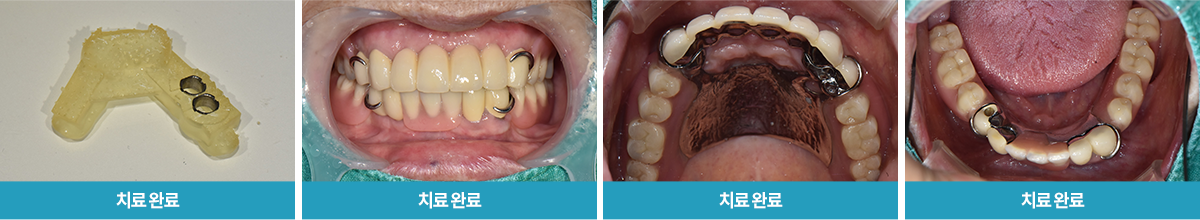

위아래 틀니 사용, 기존 치아 시큰거림, 망가짐

20번대 구치부 본 손실된 치아들 발치

/ 40번대 임플란트 식립 2달 뒤 하악 부분틀니와 함께 인상채득,

최종 보철물 세팅 완료

· 네비게이션 임플란트 / 임플란트 식립 2개월 후 보철물 체결 완료와 더불어 다량의 충치 크라운 치료 진행 case